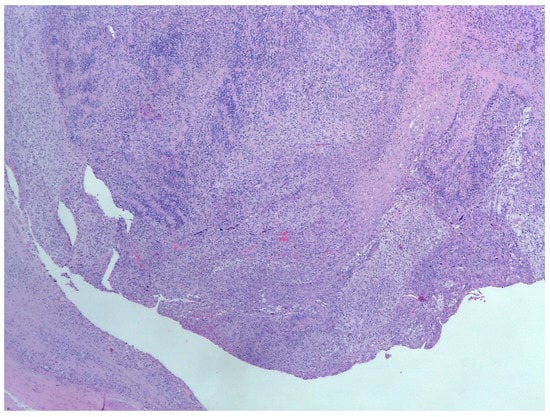

5. Histology